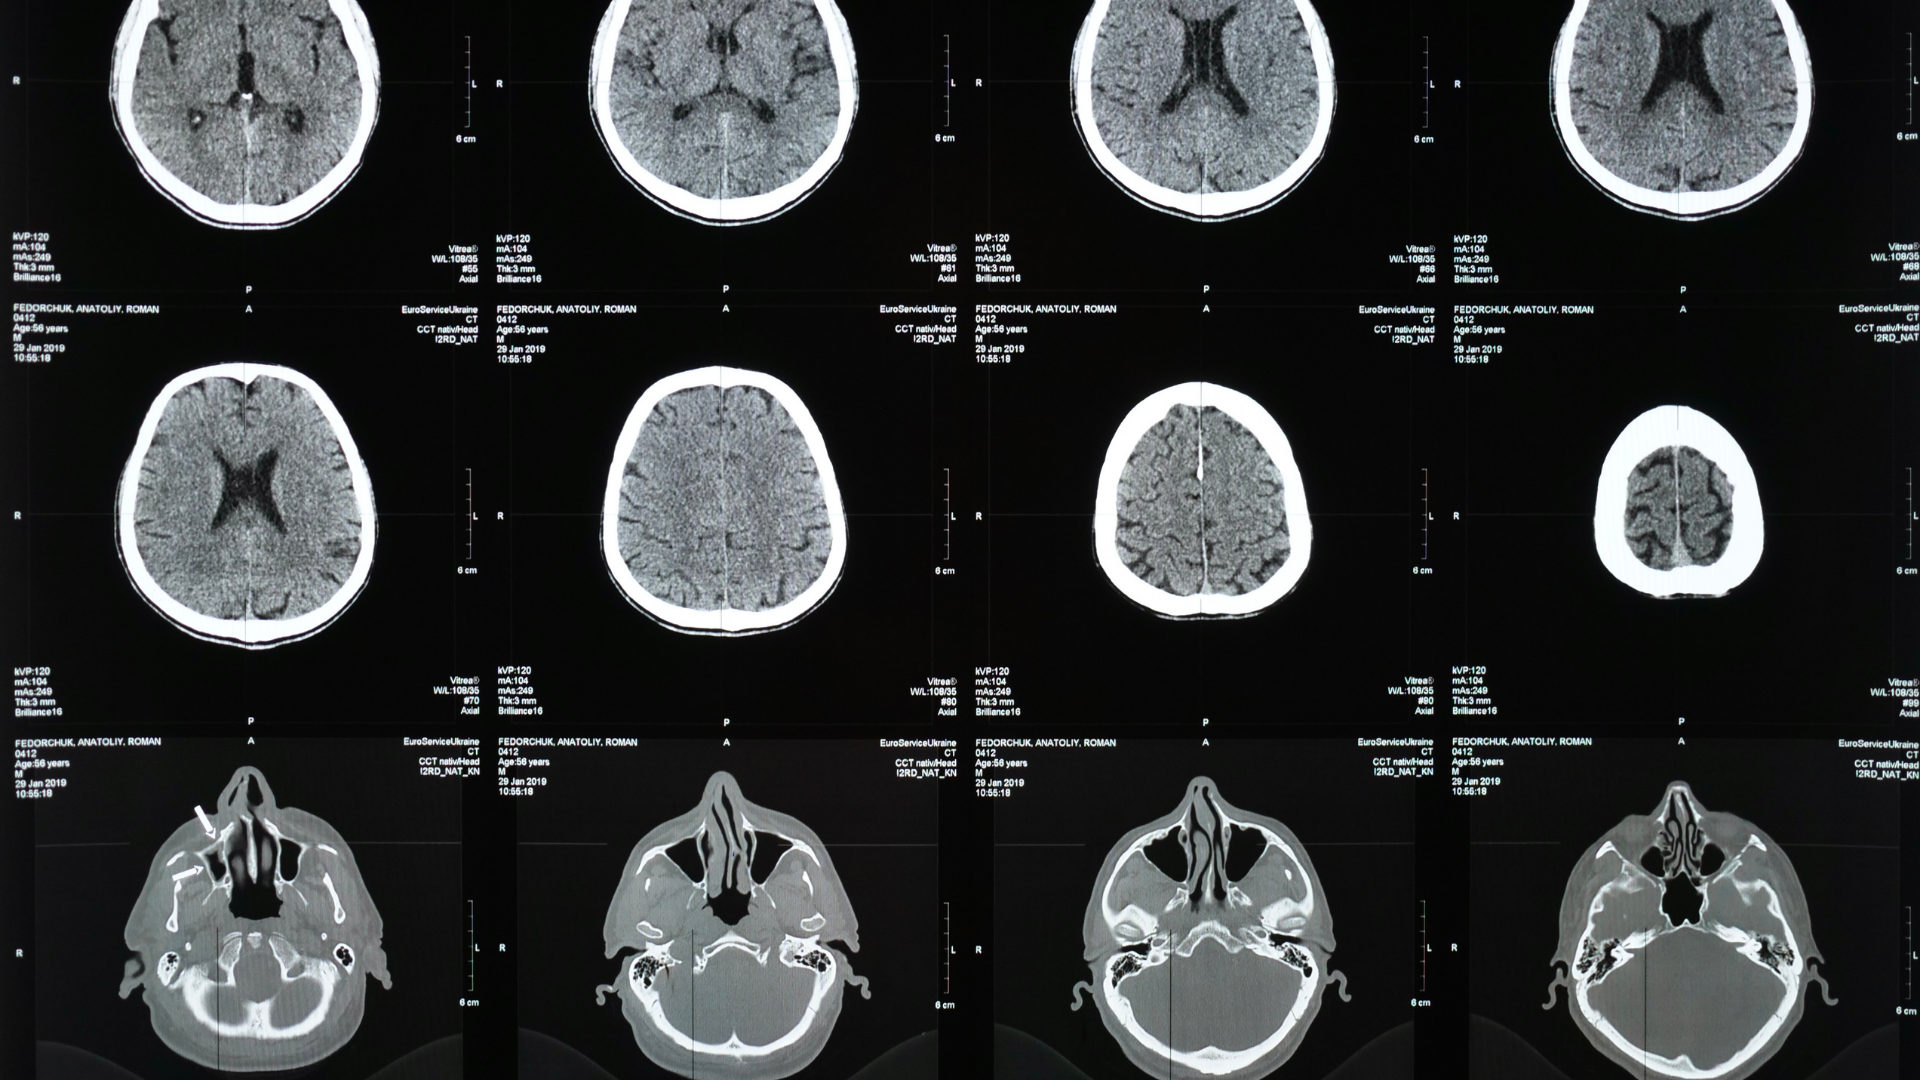

Chụp CT não là phương pháp chẩn đoán bằng hình ảnh sử dụng tia X và hệ thống máy tính để tạo ra những lát cắt chi tiết của hộp sọ và não bộ. Nhờ đó, bác sĩ có thể quan sát rõ cấu trúc xương hộp sọ và mô não. Trong trường hợp cần khảo sát mạch máu, có thể sử dụng biến thể như CT mạch (CTA) với thuốc cản quang. Phương pháp này còn được gọi là chụp CT sọ não hoặc chụp CT đầu để nhấn mạnh vị trí khảo sát.

Khi được chỉ định, nhiều người thắc mắc chụp CT não chẩn đoán bệnh gì. Dưới đây là những tình trạng cần kỹ thuật này trong thực hành y khoa:

Xuất huyết nội sọ và đột quỵ

Chụp CT sọ não có khả năng phát hiện máu tụ trong não hoặc dưới màng cứng, xác định nhanh tổn thương ở người nghi ngờ đột quỵ. Đây là yếu tố then chốt giúp bác sĩ quyết định hướng điều trị phù hợp trong cấp cứu.